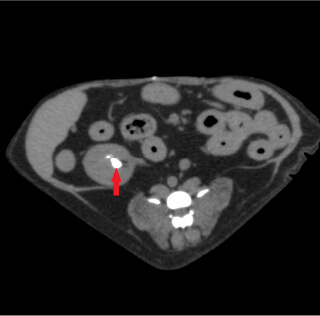

- 腹部

- 各臓器の腫瘍、

門脈体循環シャント、

結石、消化管内異物、

重積・捻転、腸閉塞